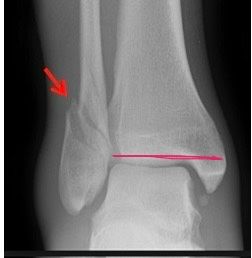

장핀으로 발목 경비인대 고정했는데 쉽게 부러질까요?

선생님 말로는 체중 100% 닿으면 쉽게 부러지는 핀이니까 조심하라고 하셨습니다

사진은 제 발목 사진이 없어서 대충 그려봤습니다

• 1번 째 사진

핀 종류마다 강도 차이가 있어 부러지기 쉬운 것도 있지만 대부분 일정 충격 이상이어야 손상됩니다 순간적으로 세게 딛었다 해도 큰 통증없이 움직임만 찌릿하다면 대개 핀이 부러졌을 가능성은 낮습니다.

하지만 계속찌르는 느낌이 든다면 핀 손상이나 위치 변화, 연부조직 자극 가능성이 있으니 확인이 필요해요!